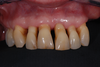

Les cas extrêmes de déchaussement peuvent être réhabilités grâce à des couronnes ou des bridges fixes supportés par des implants et reconstruisant toutes vos dents.

Après

cas traité20